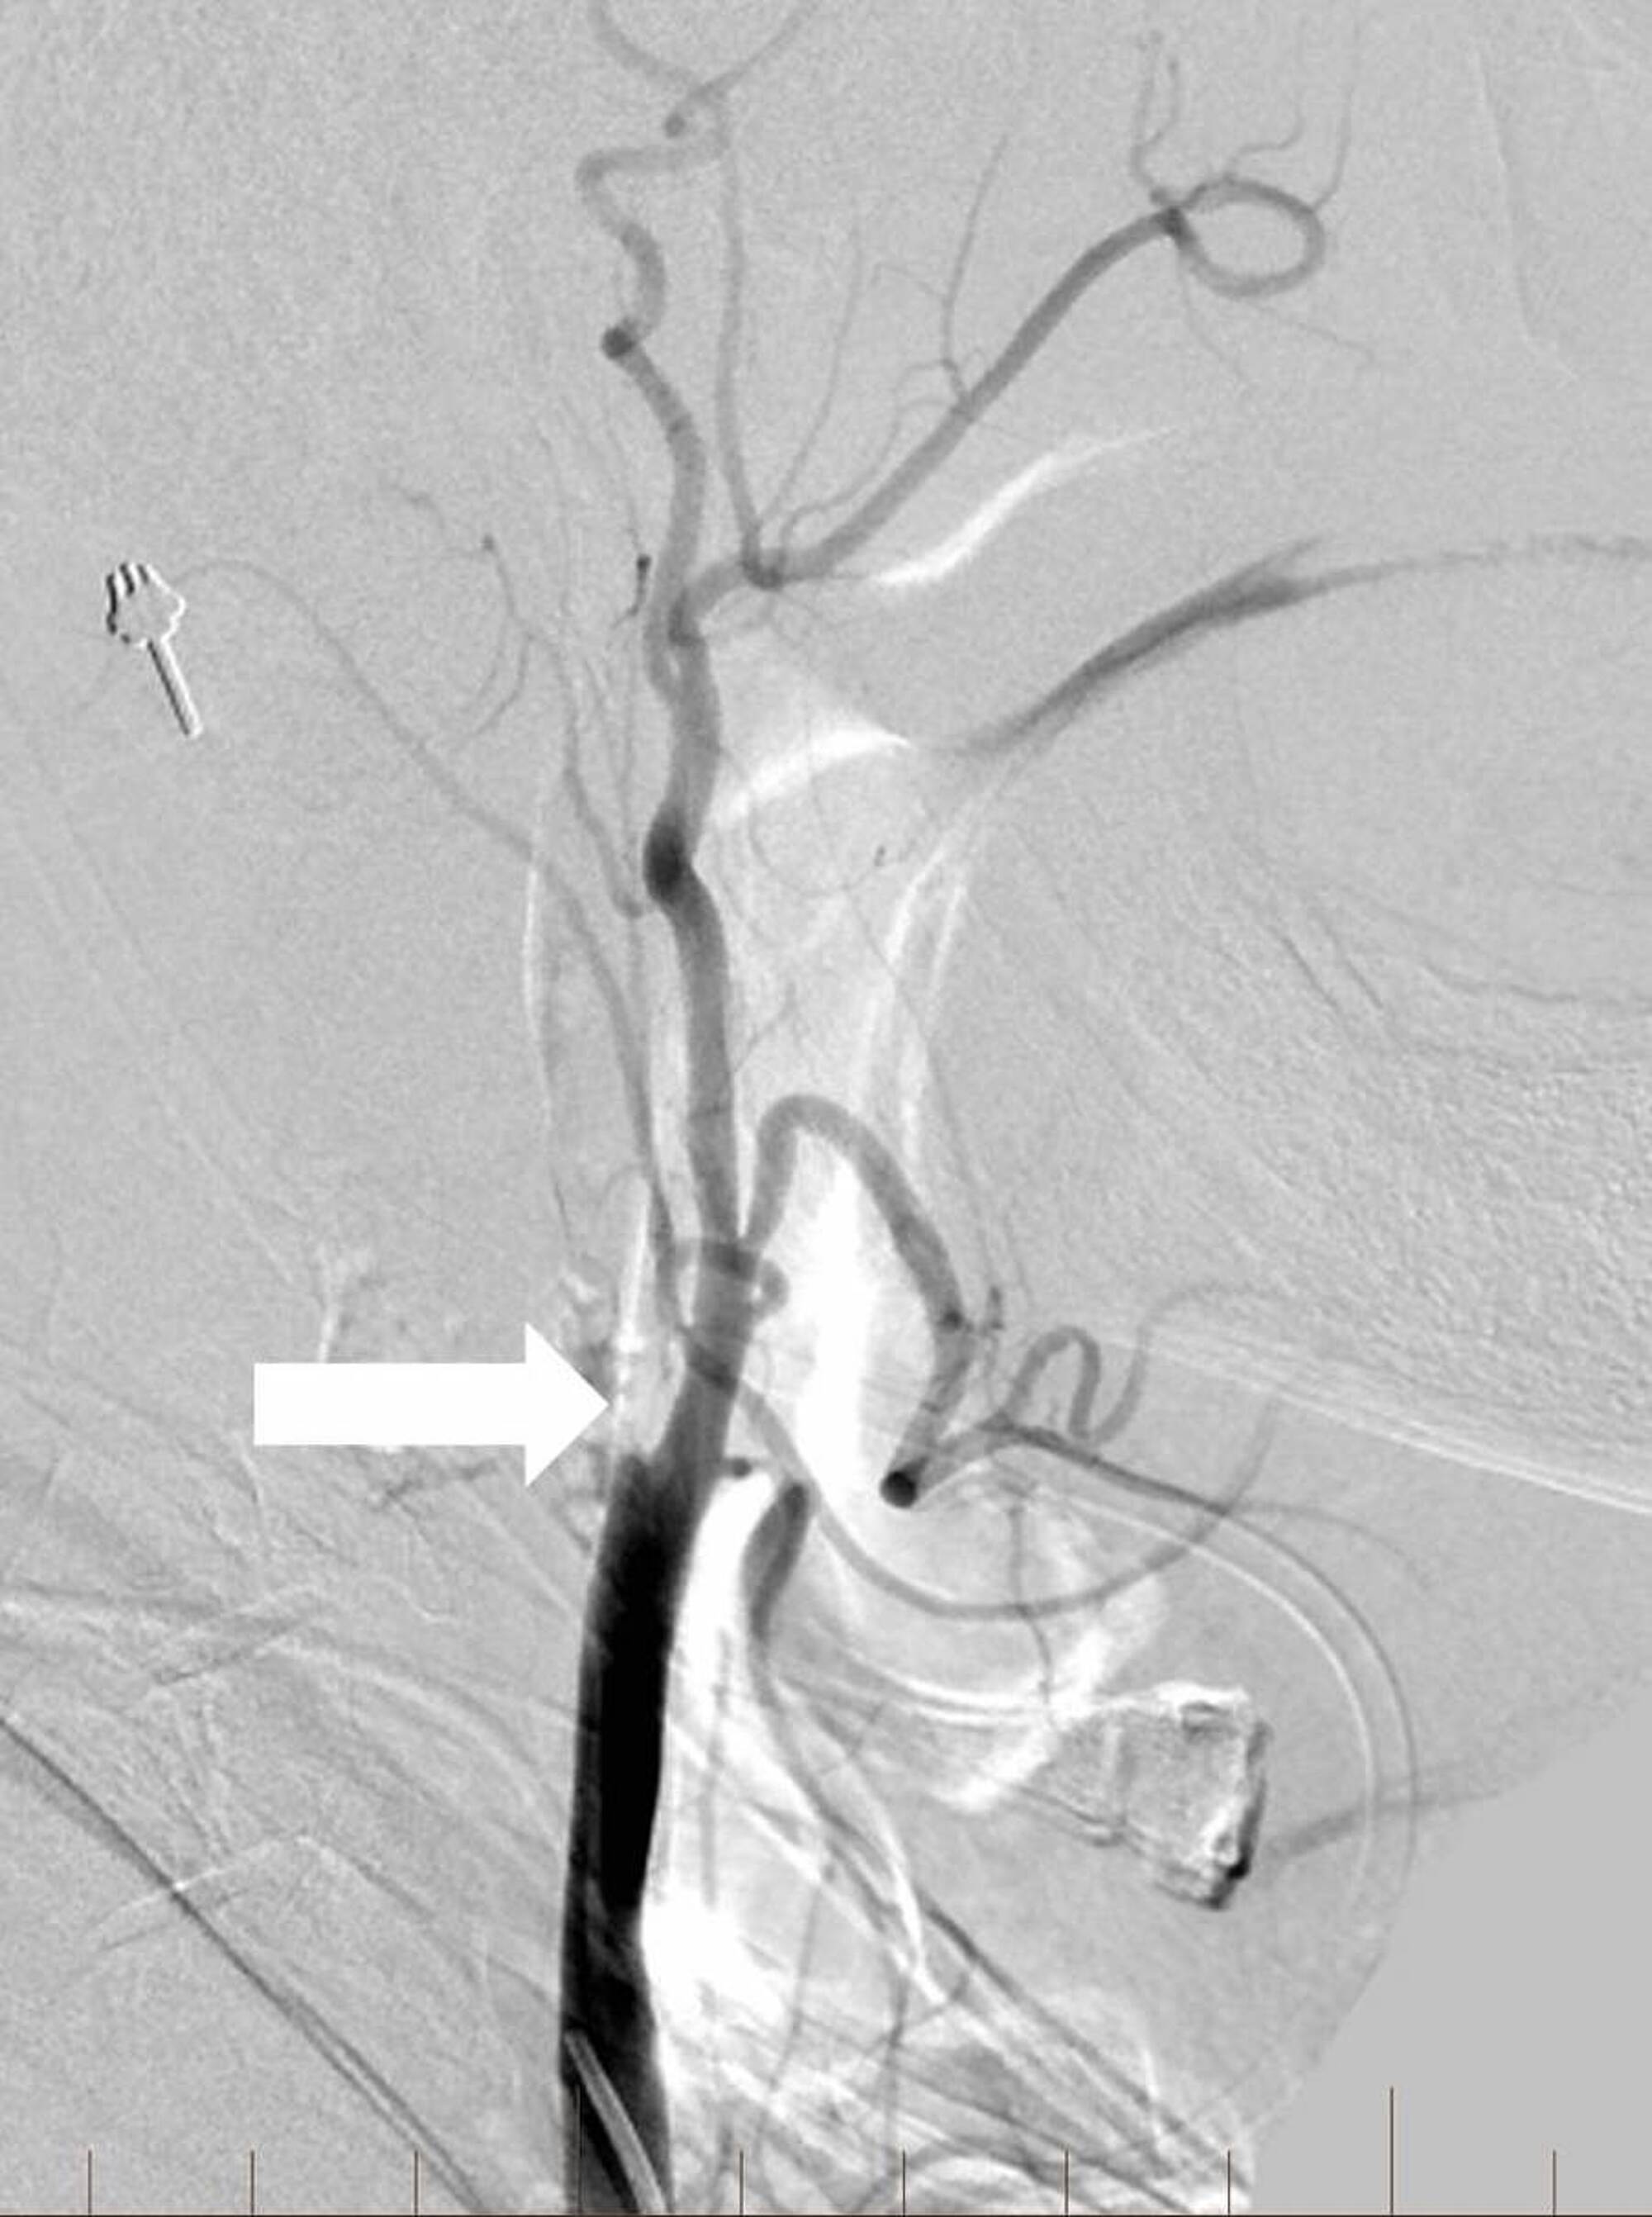

Given the previous administration of tPA, a decision was made to attempt balloon angioplasty without carotid stenting of the extracranial ICA. A 6 mm x 20 mm noncompliant balloon was positioned across the occluded proximal ICA and inflated until adequate luminal patency was restored. The thromboemboli in the supraclinoid ICA and MCA were subsequently removed by suction aspiration using an ACE 68 reperfusion catheter (Penumbra, Inc., Alameda, CA) and a direct aspiration first pass (ADAPT) technique [9]. Post-procedural right common carotid angiography demonstrated complete recanalization of the right middle cerebral and right anterior cerebral arteries without angiographic evidence of complicating features (Figure 8).

Angiography of the right common carotid artery demonstrated approximately a 40% residual stenosis at the ICA origin with no delay in the transit of contrast into the intracranial vasculature. A thrombolysis in cerebral infarction (TICI) score of three was achieved at the conclusion of the operation. Subsequent head computed tomography (CT) and magnetic resonance imaging (MRI) of the brain showed scattered infarcts in the right middle cerebral artery territory with multifocal petechial hemorrhages without frank hematoma. Compared to his initial NIHSS score of nine at presentation, he was discharged home three days later with an NIHSS of zero and no residual neurological deficits.